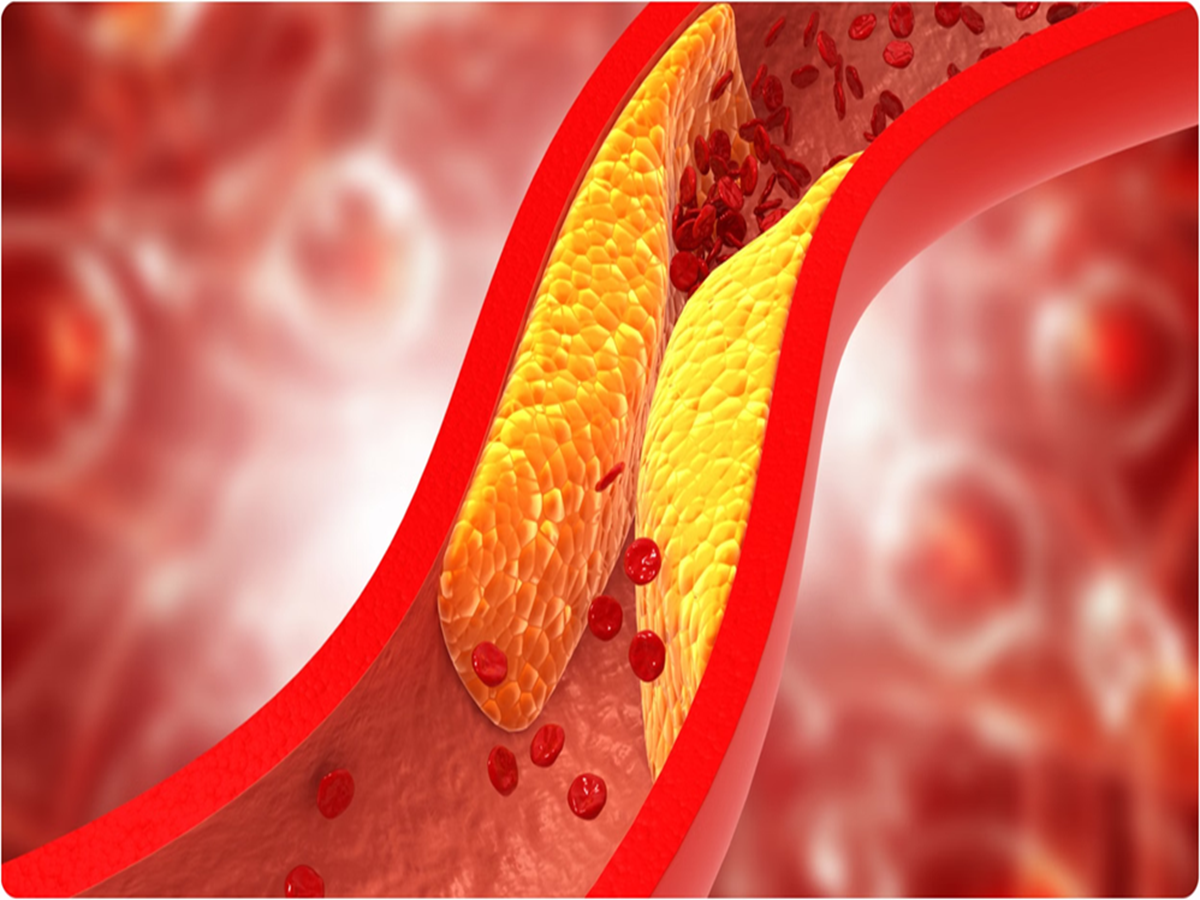

High cholesterol is a major cause of heart attacks and heart disease, but it's often called the silent killer. It gets this name because the signs of high cholesterol don't appear until the situation becomes very serious.

Cholesterol is a waxy substance found in our blood. The body needs a certain amount of good cholesterol (HDL), but if the amount of bad cholesterol increases, it starts accumulating in the arteries.

Plaque buildup - When the amount of bad cholesterol in the blood is high, it begins to stick to the walls of the arteries. Over time, it hardens and forms plaque.

Narrowing of the arteries - As plaque builds up, the arteries become narrower and stiffer. This reduces blood flow and increases blood pressure.

Blocked blood circulation - This process can occur painlessly for years. The body adapts to this change, so the patient may not feel anything.

Heart attack or stroke - When arteries become completely blocked or there is very little room for blood flow, it causes a heart attack or stroke.